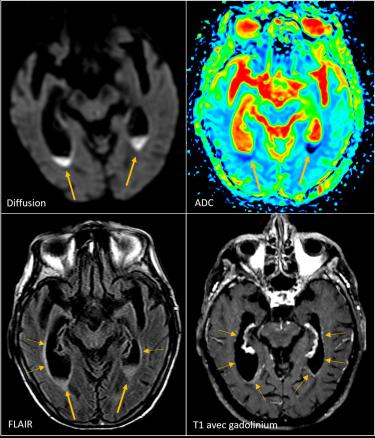

Une patiente âgée de 90 ans vivant seule chez elle, avec la visite d’aides à domicile, est hospitalisée pour une asthénie sévère associée à un syndrome confusionnel fébrile évoluant depuis quelques jours, sans point d’appel clinique. Elle est en bon état général et est sous valsartan pour une hypertension artérielle. L’examen clinique ne retrouve aucune anomalie en dehors d’une confusion fébrile sans syndrome méningé ni signe de localisation. Les hémocultures sont stériles. La protéine C-réactive (CRP) est à 126 mg, avec une hyperleucocytose à polynucléaires neutrophiles à 13 000/mm3. Le reste du bilan biologique est normal. Une ponction lombaire est réalisée en urgence  ; elle montre un liquide céphalorachidien (LCR) citrin (fig. 1) avec une protéinorachie à 3,29 g/L, une hypoglycorachie à 450 leucocytes/mm3 (36 % de polynucléaires, 75  % de lymphocytes). L’examen direct du LCR révèle des bacilles à Gram positif et la culture confirme l’identification de Listeria monocytogenes sensible à l’amoxicilline et au cotrimoxazole.  Dès les résultats de la ponction lombaire, la patiente a été mise sous amoxicilline à la dose de 200 mg/kg/24 h et de la gentamicine à 5 mg/kg/24 h a été ajoutée pour cinq jours. L’imagerie par résonance magnétique (IRM) [fig. 2] met en évidence plusieurs abcès (protubérance, cervelet) et une ventriculite bilatérale avec pus intraventriculaire (fig. 3). La patiente n’était pas immunodéprimée. La déclaration obligatoire a été effectuée. L’enquête de l’agence régionale de santé (ARS) n’a pas retrouvé de cas groupés dans l’entourage. Après six semaines d’antibiothérapie par amoxicilline intraveineuse à haute dose, la patiente a recouvré une conscience normale, sans séquelle neurologique clinique apparente, et une autonomie qui ont permis le retour à domicile.

La localisation méningée1,2 est associée dans près de la moitié des cas à des signes d’encéphalite diffuse avec des abcès intracérébraux localisés de façon prédo­minante au rhombencéphale. Des abcès nécrotiques coalescents et multiples apparaissent, entraînant des pertes de substances importantes du tissu nerveux.